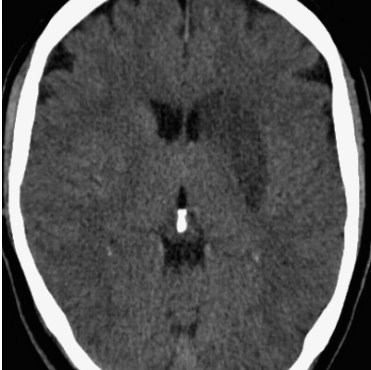

The former is a randomised-controlled trial that collected brain imaging data, primarily CT scans, from 3035 patients exhibiting stroke symptoms. The scans were conducted at two time points: immediately after the patients’ hospital admission and again between 24-48 hours later. Radiologists involved in the trial assessed the presence or absence of early ischemic signs and recorded the location of any identified lesions for positive scans. In our analysis, we considered a total of 5681 scans, of which were classified as negative (no lesion), while the remaining scans were positive. In particular, We considered 11 slices for each scan and resized each slice to . For more detailed information about the trial protocol, data collection, and the data use agreement, please refer to the following URL: IST-3 information.

4.3 Counterfactual Examples

In Figures 2 and 4 we display examples of healthy images and anomaly maps obtained with the different approaches. We can observe that f-Ano GAN is not able to generate credible counterfactuals and generally produces images of poor quality and unrealistic appearance. On the other hand, the approaches based on diffusion models are able to create more high-quality results. However, the ones obtained with CG and CFG seem to present some artifacts, which may not only impact the realism of the counterfactual examples but also the precision of the anomaly maps obtained from them. In order to better quantify the capability of these methods to accurately segment pathological areas, we compute the Dice scores of the anomaly maps they generate.